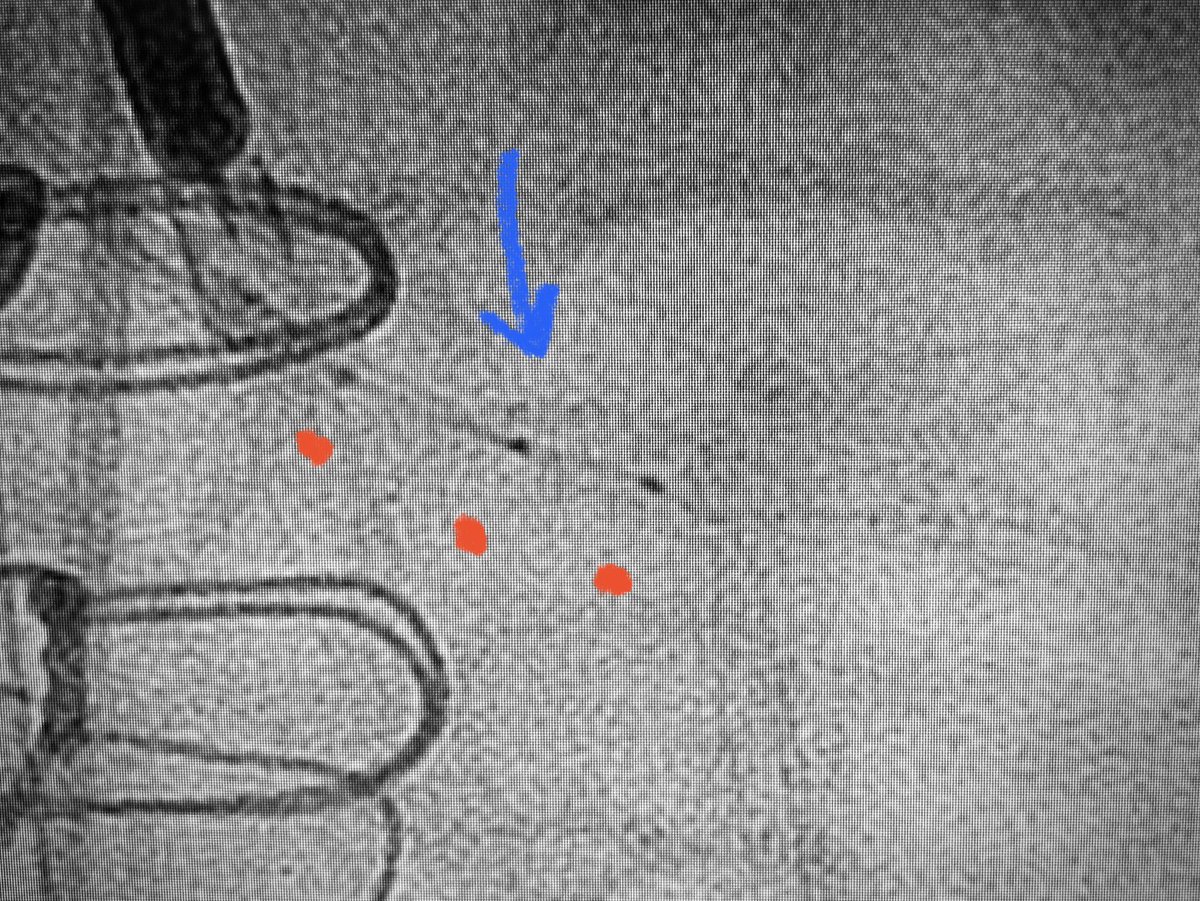

What an Ostial FLASH’d stent looks like by IVUS 👀 (Figs 1,2 before ➡️ Figs 3,4 after) Stop “nailing the ostium” — Just dangle the stent a little & @OstialFLASH it!